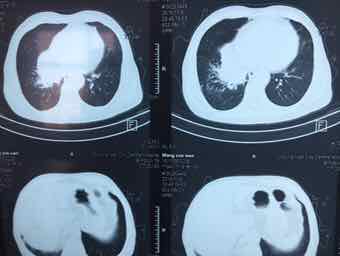

男,74岁,咳嗽咳痰3个月,无发热,无胸痛,无盗汗,无咳血。右肺占位性质待查?完善气管镜检查